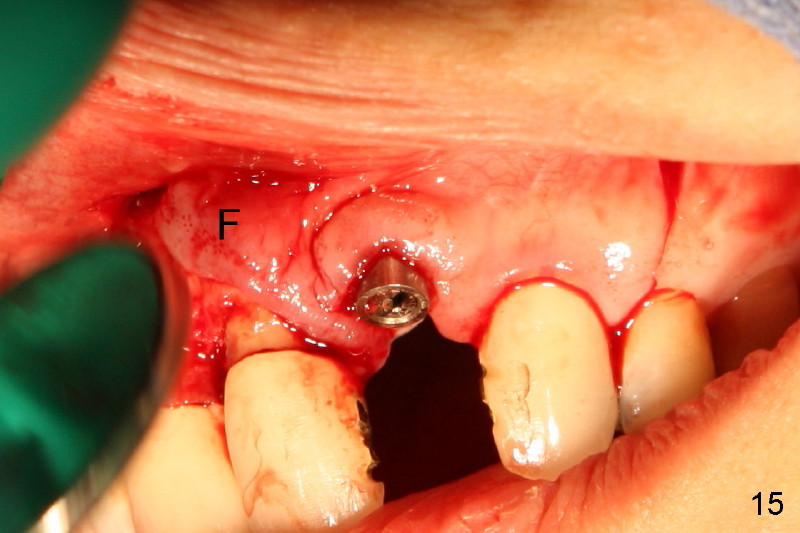

Segmental Osteotomy for Misplaced Implant

This corrective surgery was performed by Dr. Bernee Dunson.

Xin Wei, DDS, PhD, MS 1st edition 12/21/2011, last revision 12/23/2011